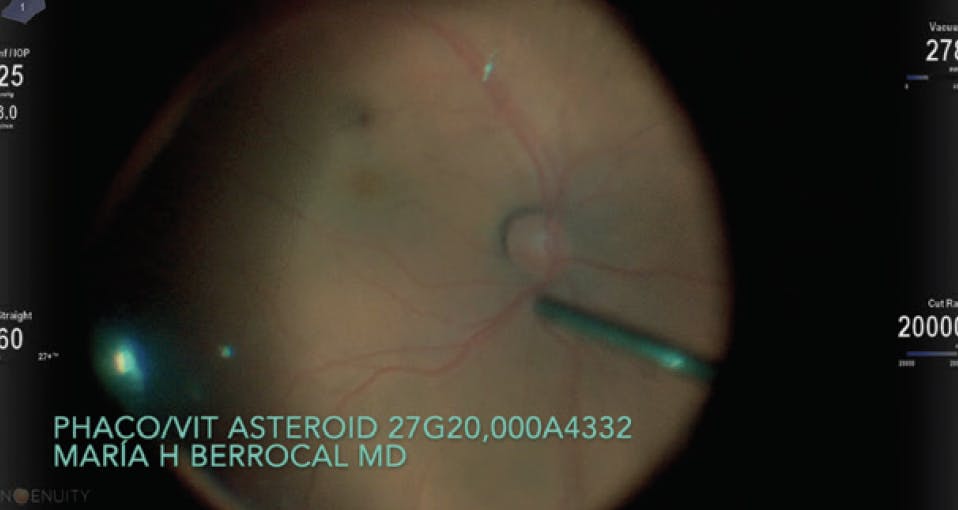

Phacovitrectomy in a Patient With Asteroid Hyalosis

A 78-year-old man presented to my clinic with 20/200 VA. Significant cataract and asteroid hyalosis were observed during examination. His condition and age dictated reduced surgical burden. Given my comfort with combined procedures, I elected to perform a phacovitrectomy with 27-gauge instrumentation using a rate of 20,000 cuts per minute and the NGENUITY 3D Visualization System (Alcon).

Figure 1. Phacoemulsification was performed without incident during the first stage of phacovitrectomy.

Figure 2. Dense asteroid hyalosis was present at the beginning of the vitrectomy stage of the phacovitrectomy.

I removed the crystalline lens without incident and placed a monofocal IOL (Figure 1). Dense asteroid hyalosis was encountered at the outset of vitrectomy (Figure 2). It took approximately 11 minutes to clear most of the vitreous (Figure 3). The surgery was efficient due to my use of 20,000 cuts per minute on the 27-gauge instruments. A final inspection of the periphery to clear up any remaining tissue was performed (Figure 4). The patient’s final postoperative VA was 20/30.